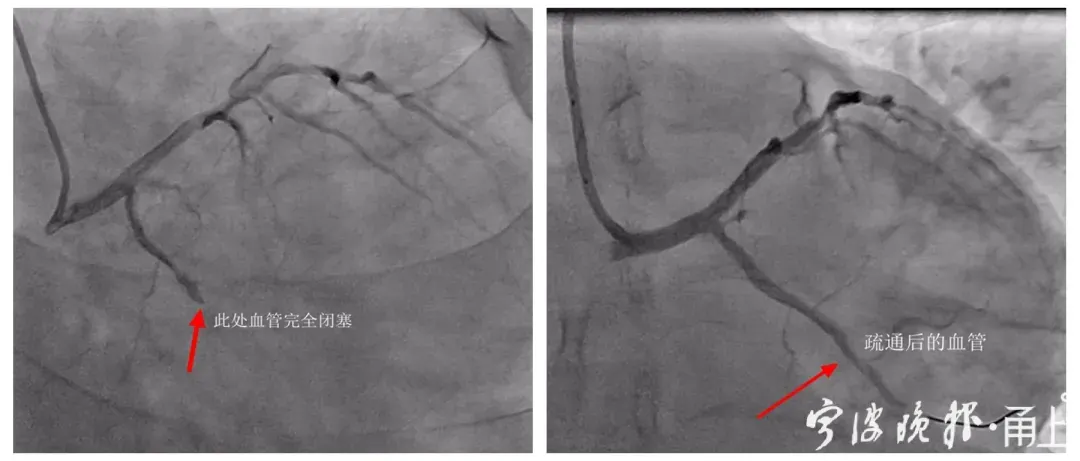

检查过程中,医生发现小戴心脏内冠状动脉的回旋支已是完全闭塞状态,随时可能有生命危险。考虑到他还很年轻,两位专家征得患者及家属同意后,决定暂不放置支架,先通过球囊扩张术开通闭塞的血管。经过近一周的后续治疗,日前已康复出院。